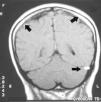

Figura 2. Imagen potenciada en T1, hiperdensidad en ambas regiones talámicas

Se trata de una paciente de 58 años de edad, con antecedentes personales de hipertensión arterial, histerectomía y anexectomía bilateral, con síndrome menopáusico en tratamiento sustitutivo con raloxifeno (modulador selectivo de los receptores estrogénicos). Ingresa en nuestra Unidad por cuadro confusional de 48 horas de evolución, acompañado de trastornos del equilibrio e hiporreflexia en miembro inferior derecho. Se realiza tomografía axial computarizada (TAC) craneal de urgencia donde se aprecia hiperdensidad localizada en seno longitudinal superior (seno sagital) compatible con trombosis del mismo. Dado el anterior hallazgo, se efectúa una resonancia magnética nuclear (RMN) cerebral de urgencia, donde en imágenes potenciadas en T1, en los tres planos, se visualiza hiperseñal persistente a nivel del seno longitudinal superior, recto trasverso y sigmoideo izquierdo (fig. 1 [flechas negras]), acompañándose de edema en ambas regiones talámicas (fig. 2 [flechas negras]). Con todo ello se le diagnostica de trombosis venosa del seno longitudinal superior, recto trasverso y sigmoideo izquierdo, así como de edema bitalámico. La paciente recibió tratamiento con heparina sódica en perfusión continua, vasodilatadores para el control de la presión arterial, con mejoría clínica hasta alcanzar un GCS (Glasgow Coma Scale) de 15 puntos sin focalidad a los tres días de su ingreso. El raloxifeno fue suspendido, no recidivando el cuadro clínico.